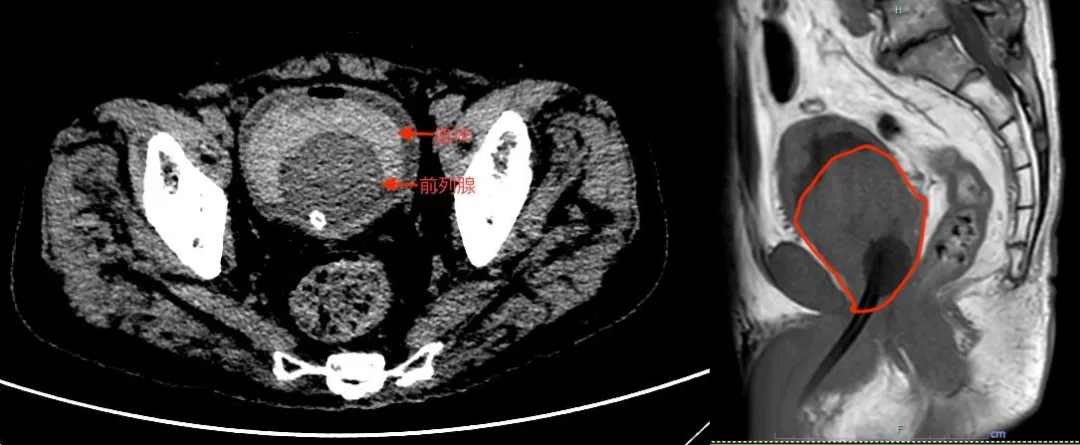

负责接诊的泌尿外科副主任医师王文佳给老人完善了影像检查,泌尿CT检查提示膀胱内被血块填塞,前列腺体积巨大,凸入膀胱,前列腺质量有140多克(正常成人前列腺一般在12~20克左右,超过75克即为最严重的前列腺四度增生)。王文佳与家属交代病情,考虑前列腺增生合并反复出血,立即收治入院治疗。

CT影像显示突入膀胱的前列腺及膀胱内血块